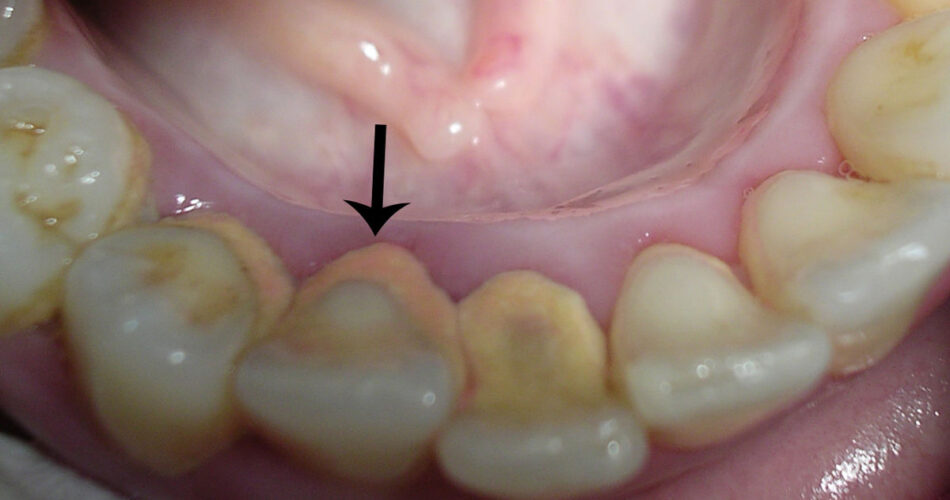

คราบหินปูนเกิดจาก คราบจุลินทรีย์ (Plaque) ที่สะสมอยู่บนผิวฟัน คราบจุลินทรีย์เหล่านี้เป็นแบคทีเรียที่รวมตัวกับเศษอาหารและน้ำลาย เมื่อไม่ได้รับการทำความสะอาดอย่างเหมาะสม คราบเหล่านี้จะเริ่มแข็งตัวและกลายเป็น หินปูน ซึ่งไม่สามารถกำจัดออกได้ด้วยการแปรงฟันเพียงอย่างเดียว

หินปูนที่สะสมอยู่ตามขอบเหงือกทำให้เกิดการอักเสบของเหงือก หรือที่เรียกว่า เหงือกอักเสบ (Gingivitis) ซึ่งมีอาการเหงือกบวม แดง และมีเลือดออกขณะแปรงฟัน หากปล่อยไว้อาจพัฒนาเป็น โรคปริทันต์ (Periodontitis) ซึ่งเป็นอาการรุนแรงขึ้น อาจทำให้ฟันโยกและหลุดร่วงได้

หินปูนเป็นแหล่งสะสมของแบคทีเรียที่ทำให้เกิดกรด ซึ่งจะไปกัดกร่อนสารเคลือบฟัน ทำให้เกิด ฟันผุ ได้ง่ายขึ้น หากปล่อยให้หินปูนสะสมต่อไป อาจส่งผลให้เกิดการทำลายกระดูกที่รองรับฟัน ทำให้ ฟันโยกหรือหลุดร่วง ได้ในที่สุด